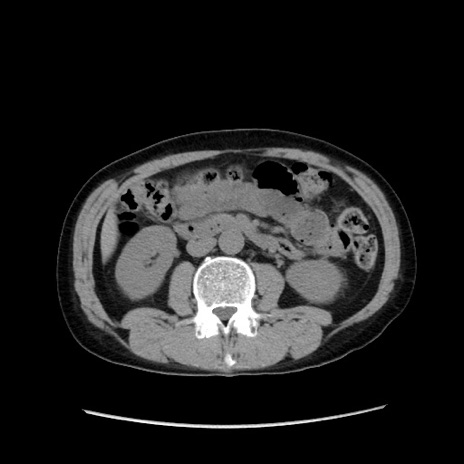

症例37(横断像)

【症例】40歳代 男性

【主訴】腹痛

【現病歴】4時間ほど前に電車に乗車中に臍部上より腹痛出現。徐々に増悪し起立困難となり、救急外来受診。生ものは数日食べていない。今朝お雑煮を食べた。

【身体所見】BT 36.8℃、BP 117/84mmHg、HR 91/min、SpO2 97%、苦悶様、腹部:臍上部広範囲圧痛あり、反跳痛±

【データ】WBC 8100、CRP 0.03